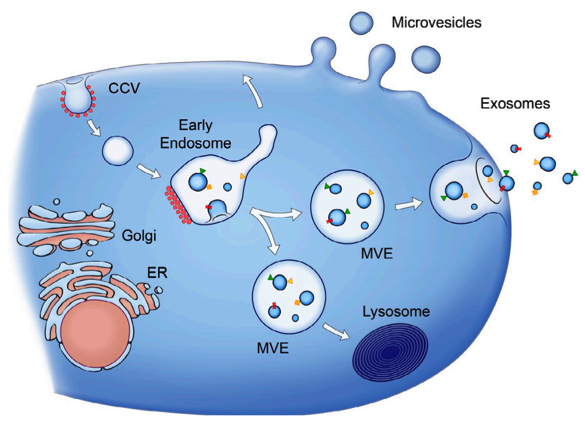

?近日,為期三天的中國國際美博會在廣州圓滿落幕。鄭州源創基因科技有限公司攜核心科技產品——腫瘤特異性多肽及源泌體系列驚艷亮相,以細胞科技與專業服務實力,在美博會掀起生物護膚熱潮,吸引眾多專業人士駐足洽談。

?衰老是一種內在的生物過程,其特征是系統性改變逐漸損害生理完整性并增加對與年齡相關的疾病的易感性,最終導致死亡。衰老的標志包括細胞衰老、基因組不穩定性、表觀遺傳改變、蛋白質穩態喪失、干細胞耗竭、慢性炎癥和細胞間通訊改變。